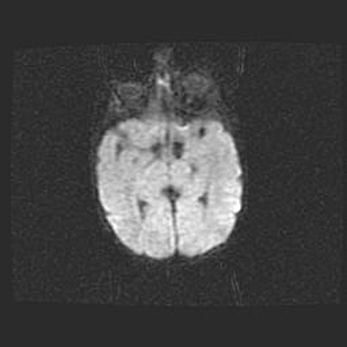

Сообщающаяся гидроцефалия. Кистозная энцефаломаляция головного мозга.

Возраст: 3 месяца 4 дня

Вес: 3100 г

Пол: женский

Окружность головы: 34 см

Срок гестации: 31 неделя

Кистозная энцефаломаляция головного мозга - одна из форм поражения головного мозга в детском возрасте. Характеризуется возникновением множественных и распространённых кист в коре, белом веществе и подкорковых образованиях головного мозга у плодов, новорождённых и детей раннего возраста. Развитие кистозной энцефаломаляции связано с внутриутробной асфиксией и гипотонией, родовой травмой, тромбозом синусов, пороками развития сосудов, инфекциями, сепсисом и другими причинами. Наиболее значимые инфекционные агенты: вирусы простого герпеса, цитомегалии, краснухи, токсоплазмы, энтеробактерии, золотистый стафилококк и другие.